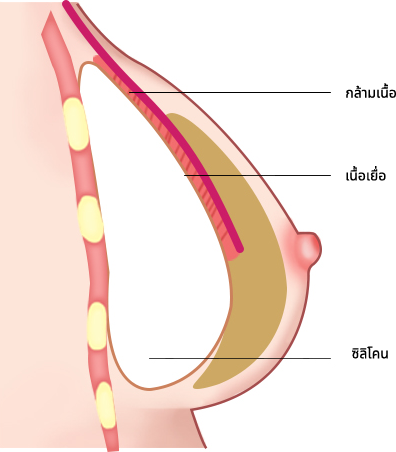

โดยเสริมซิลิโคนที่ด้านบนของกล้ามเนื้อและด้านล่างของเนื้อเยื่อ ทำให้มีลักษณะคล้ายกับซิลิโคนมากที่สุด

สามารถสร้างรูปร่างของหน้าอกได้ การเคลื่อนย้ายของซิลิโคนหรือรูปร่างของหน้าอกจะไม่เปลี่ยนแปลง

เมื่อเสริมซิลิโคนใต้กล้ามเนื้อ ความเจ็บปวดจะน้อยกว่ามาก การกลับมาทำงานปกติจะเร็วขึ้น และเยื่อหุ้มสมอง

การเพิ่มชั้นเดียวสามารถปรับปรุงการสะท้อนของซิลิโคน และการสัมผัสจะคล้ายกับการสัมผัสของหน้าอกจริง ๆ

วิธีการใส่ซิลิโคนบนกล้ามเนื้อ ,ใส่ซิลิโคนใต้เนื้อเยื่อ

เป็นวิธีการผ่าตัดที่เสริมข้อเสียของวิธีใช้สายเดรนและวิธีใช้กล้ามเนื้อ และรวมข้อดีเข้าด้วยกัน

เป็นวิธีการผ่าตัดสามารถสร้างรูปร่างตามธรรมชาติได้

ไม่เหมาะสำหรับเนื้อเยื่อใต้ผิวหนัง (ไขมัน) น้อย

ส่วนที่มีกล้ามเนื้อจะไม่ค่อยยืดออก